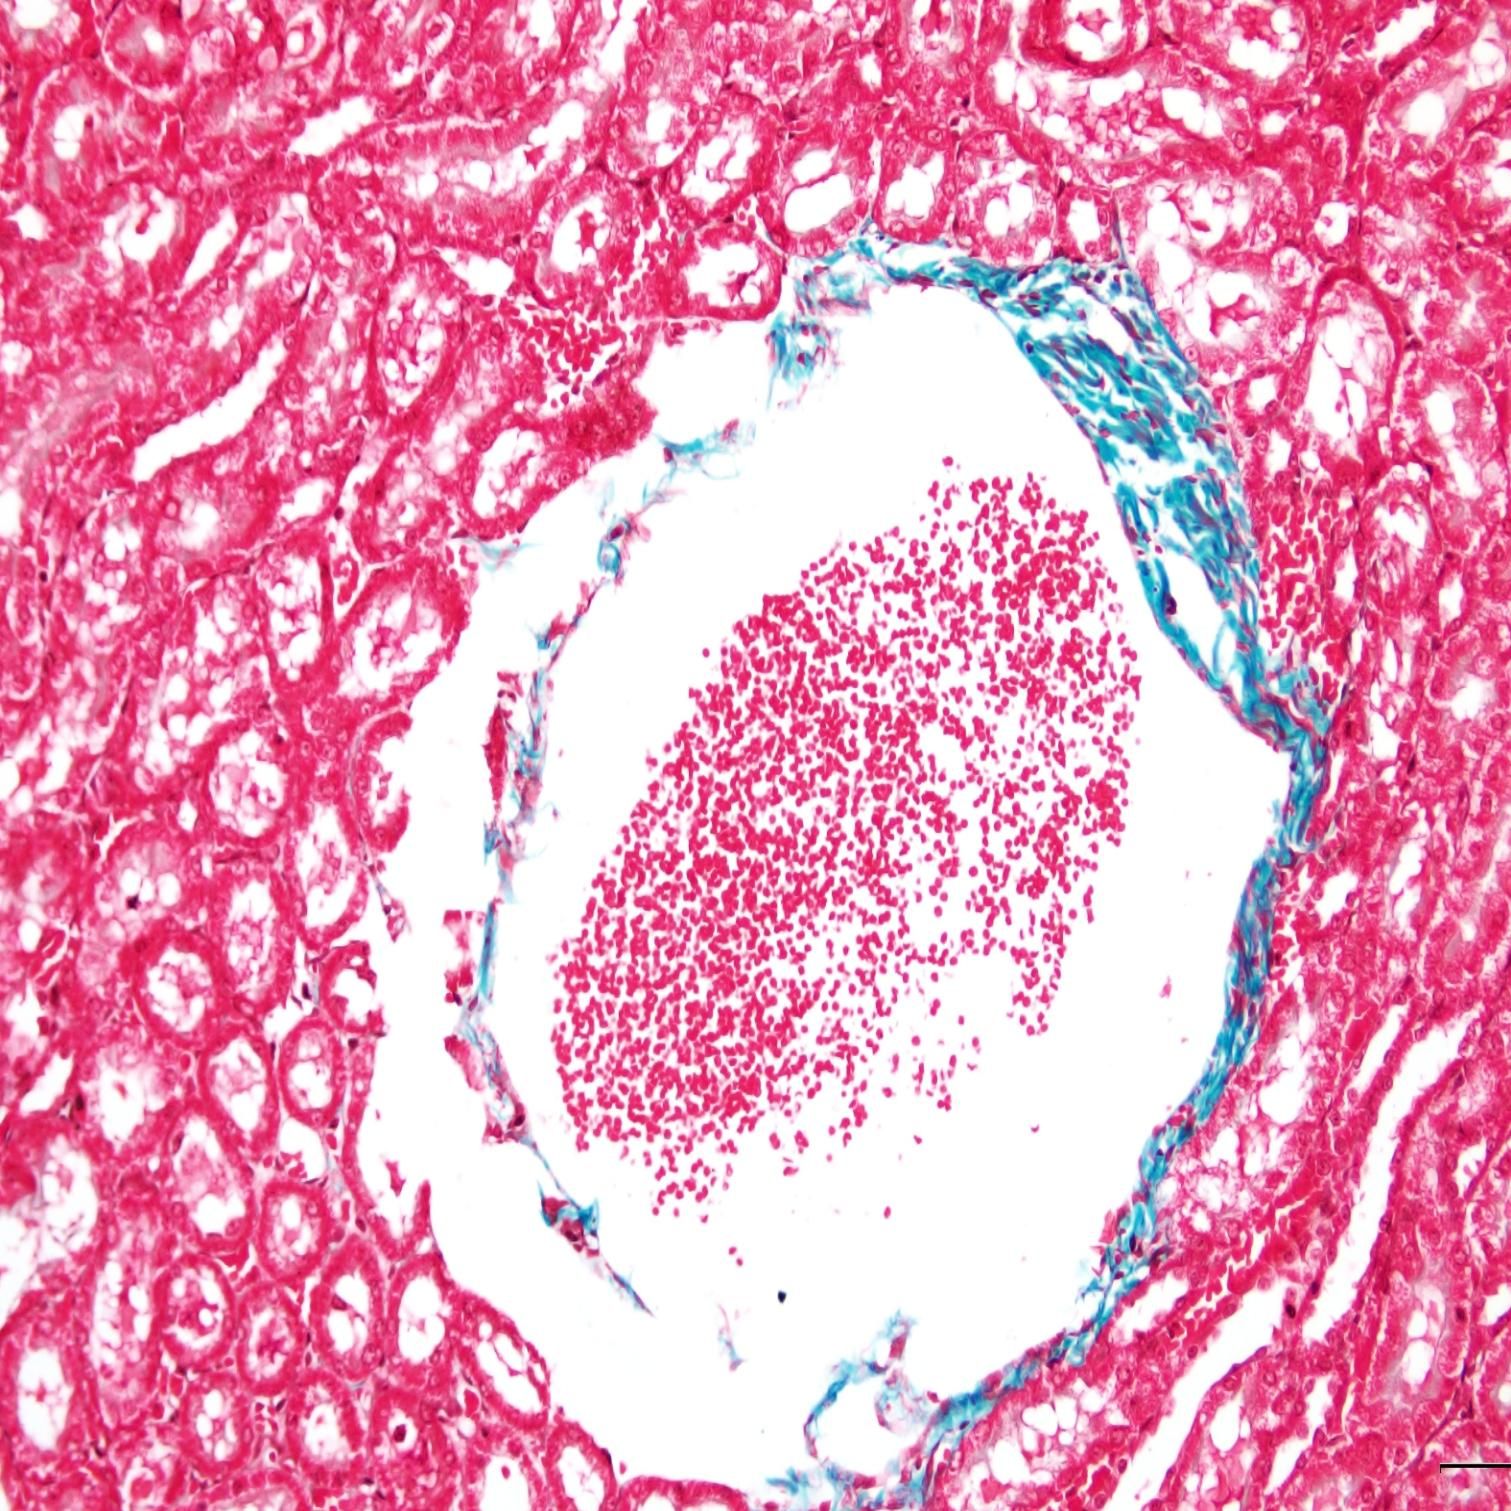

完成以上步驟后,切片中的膠原纖維、黏液和軟骨將呈現(xiàn)藍(lán)色(如果使用淺綠色液體,則呈現(xiàn)綠色),細(xì)胞質(zhì)、肌肉、纖維素和神經(jīng)膠質(zhì)將呈現(xiàn)紅色,而細(xì)胞核將呈現(xiàn)黑色和藍(lán)色。